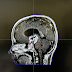

Dr. M Abid Saleem.Gamma Knife Radiosurgery Center. Dow University Hospital.Ojha Campus. Karachi.

Gamma Knife Radiosurgery : Introduction

New Gamma Knife 'ICON' at DOW Ojha campus.